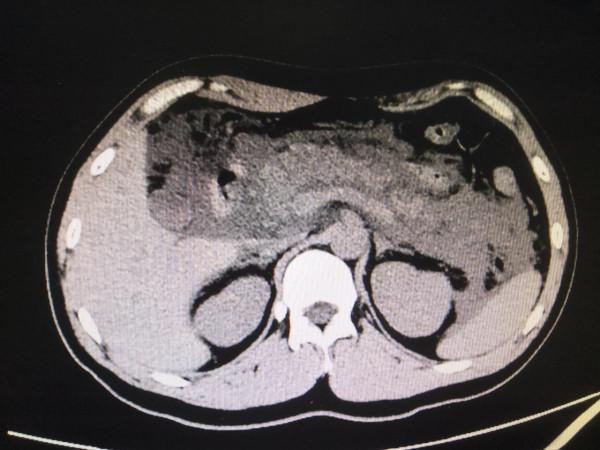

我跟過去做的,CT一掃下來,我就想到急性出血性胰腺炎。

回來診斷性腹穿抽出粉紅色腹水,送檢。